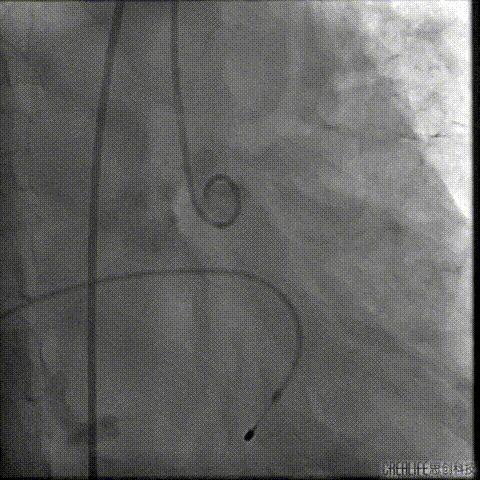

经桡冠脉保护

置入Venus-A32号瓣膜并释放

复查造影

撤出冠脉保护

再次复查造影

经瓣架网眼挂上指引管

反复确认指引管经瓣架网眼

指引管经瓣架网眼

经网眼置入导丝

置入4.0mm*23mm微创冠脉支架

定位并释放支架

退出球囊扩张突入瓣架部位

复查冠脉造影

多体位复查冠脉造影